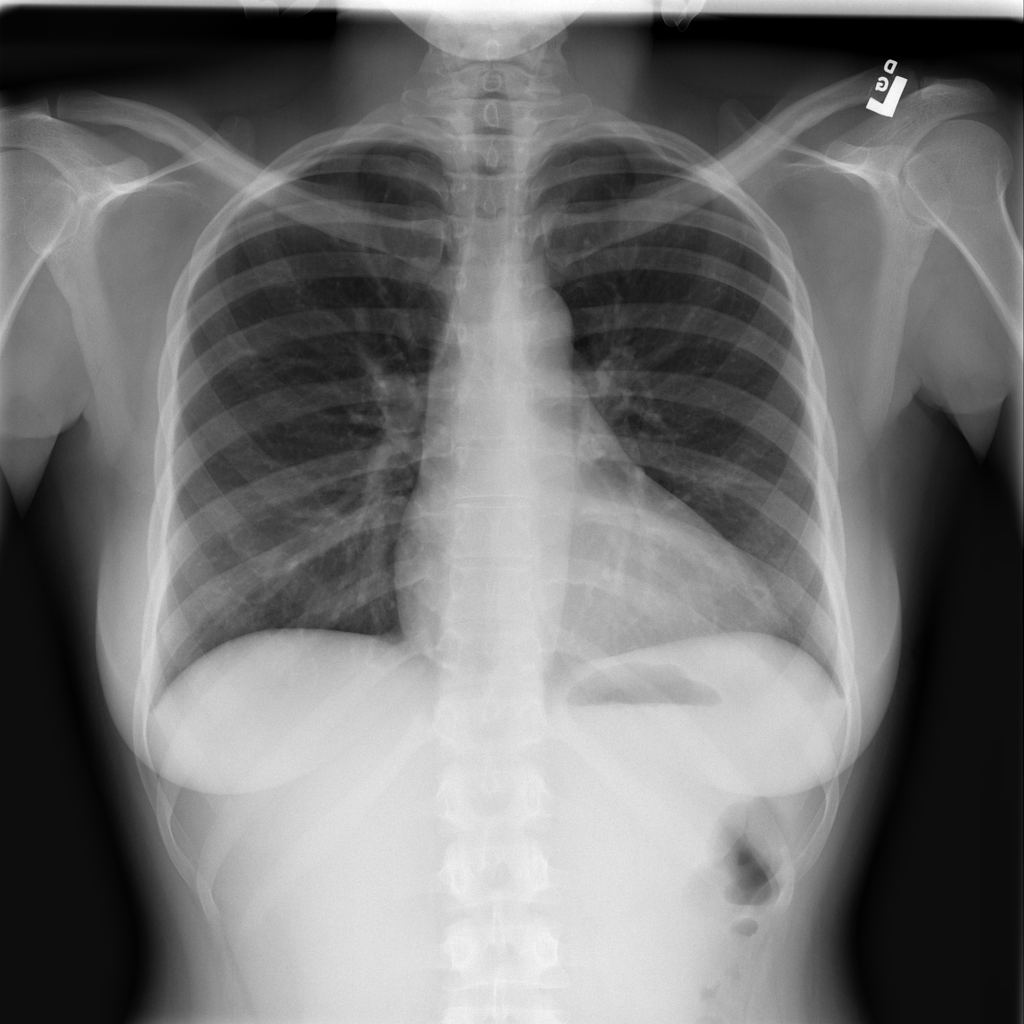

PAT-3F76 · IMG-000Cardiomegaly

PAT-3F76 · IMG-000

PA